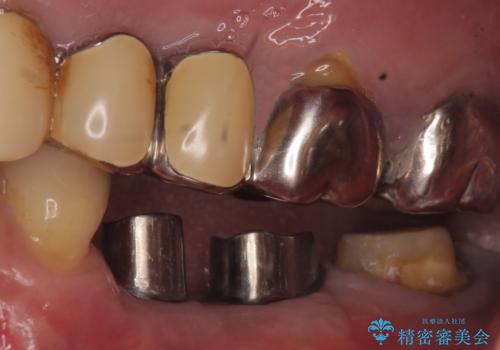

- 左下奥歯が虫歯で抜歯になってしまったため、インプラントにしたいといらっしゃった方の症例です。

欠損部位である左下5、6番目にインプラントを埋入し、オールセラミッククラウンによる補綴を行いました。

左下7番目は再根管治療を行い、オールセラミッククラウンによる補綴を行いました。

カスタムアバットメントについて

カスタムアバットメントは患者様それぞれの歯茎に合わせて製作されたオーダーメイドのアバットメントです。

既製のアバットメントに比べ適合がよく、高い清掃性を誇ります。